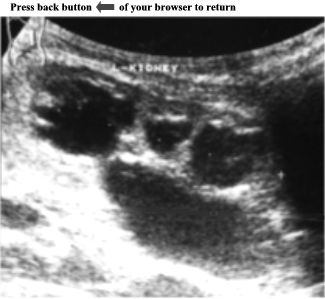

CASE

5:

Ultrasound

examination

of

an

asymptomatic

adult

patient.

Left

kidney

is

enlarged

and

shows

numerous

anechoic

areas

in

the

cortex

medulla.

These

vary

size

their

margins

are

irregular.

largest

one

measures

3.3cm

X

1.6cm.

Further

reveals

right

as

well.